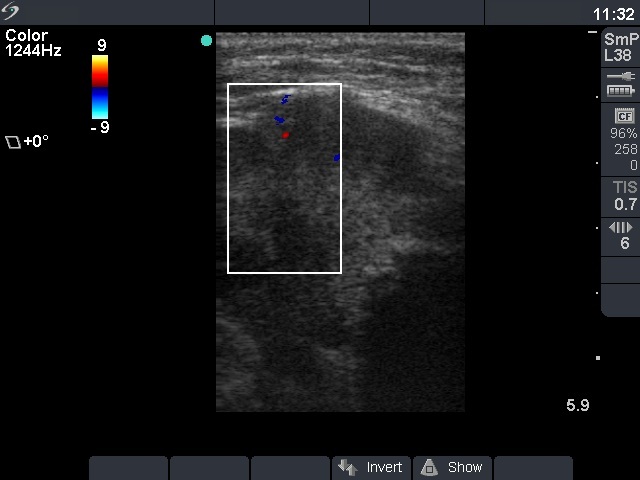

Ultrasonography: there was a hypoechogenic, inhomogeneous nodule occupying almost the entire left thyroid. The nodule spread substernal. The lesion contained microcalcifications and had irregular borders. The intranodular blood flow was decreased.